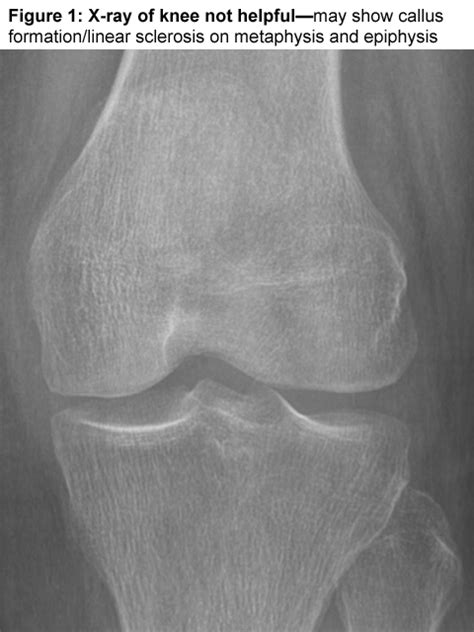

Niimi r, hasegawa m, sudo a, uchida a. Insufficiency subchondral fracture of the femoral condyle is commonly seen in elderly women with decreased bone density. 10:30 nabil ebraheim 32 127 просмотров. Yamamoto t, takabatake k, iwamoto y. Histopathologic correlation with mri}, author={t. The fracture line usually exits through the intercondylar notch. Subchondral area in the weight bearig surface of medial femoral condyle surrounded by low signal intensity in the femoral condyle with undulating hypointense lines demarcating bone infarction (figure 2). A femoral fracture is a fracture of the femur (thigh bone). Mri can identify subchondral insufficiency fractures. Figure 1 typical aspect of a subchondral insufficiency fracture of the medial femoral condyle. Subchondral insufficiency fracture of the femoral head resulting in rapid destruction of the hip joint: Subchondral insufficiency fracture with rapid collapse of the femoral head in a patient with turner's syndrome. Tokuya s, kusumi t, yamamoto t, sakurada s, toh s. The term insufficiency fracture is often applied to subchondral bone changes seen on knee magnetic resonance images (mris) (figure 1). And 6 cm proximal to the most distal point of the medial femoral condyle (dencker 1963), or 3) the diaphyseal section between the boundaries of the lower edge of the lesser trochanter and of. • most common of the medial femoral condyle. The femoral condyles form the trochlear groove that provides the articulating surface of the femur.